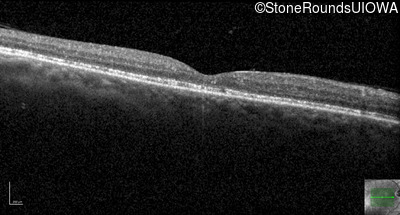

Age at visit: 69 years

This 69 year old man has had slightly subnormal acuity his entire life.